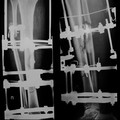

промежутке, признаков нарушения кровоснабжения не выявлено. Выполнено изменение

внутрифутлярного давления на левом бедре прибором страйкер, давление составило 70 в

переднем и 74 в заднем футляре. АД 150/90 мм. рт. ст. Спустя 2 часа исследование повторили без

динамики.

Основываясь на этих данных диагностирован компартмент синдром, принято решение

О

о выполнении фасциотомии. По наружной поверхности левого бедра произведен линейных разрез

начиная чуть ниже большого вертела и заканчивая надмыщелковой областью. После рассечения

кожи в рану начали выступать имбибированные мышцы. Далее рассечена фасция, при этом в

проекции перелома омечается разрыв мышцы откуда дренировалась гематома.

После удаления

гематомы отмечено продолжающееся артериальное и венозное кровотечение средней/малой

интенсивности. Поиски источника не увенчались успехом. Произведена фиксация перелома

аппаратом на 4 стержнях. Рана тампонирована, произведена интраоперационная ангиография,

при которой выявлена экстравазация контраста в проекции перелома. Вызван сосудистый

хирург. Произведен проксимальный контроль гемостаза, после чего начата ревизия сосудов в

проекции перелома: выявлено повреждение ветви бедренной артерии. Произведен гемостаз. На

этот момент интраоперационная кровопотеря составила более 1500 мл, перелито 4 дозы крови,

1000 мл плазмы.